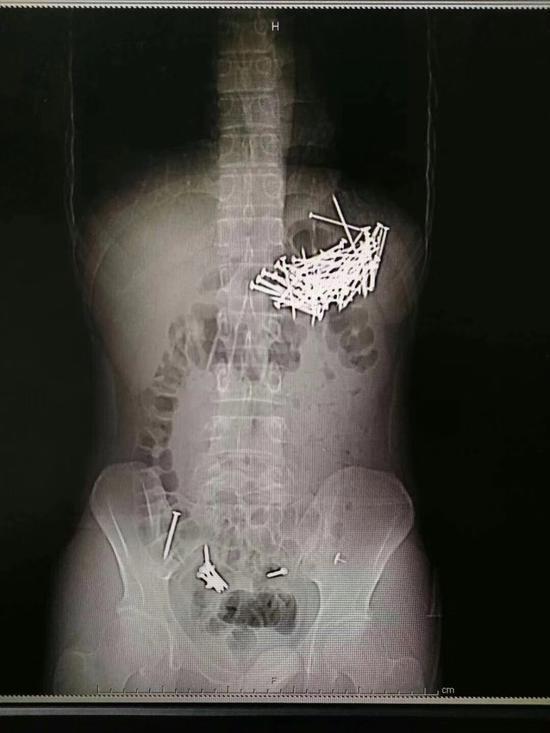

肚中取出87根铁钉:2018年8月9日晚,郴州市第一人民医院医生从25岁的小伙唐某体内取出87根铁钉。小伙吞铁钉自杀,而且吞了87根铁钉,医生通过手术从他的肚中取出铁钉,小伙获救。

8月9日晚上7点左右,经过4个小时的忙碌,医生从小伙子的腹腔和胃部等取出共87根铁钉,每根钉子大约四五厘米长。

手术医生胡志辉介绍,这个小伙子吞食了87根铁钉和7枚图钉,其中6枚图钉被病人自行排出,目前余下一枚图钉在直肠附近,由于体积较小,病人应该可以自行排出。